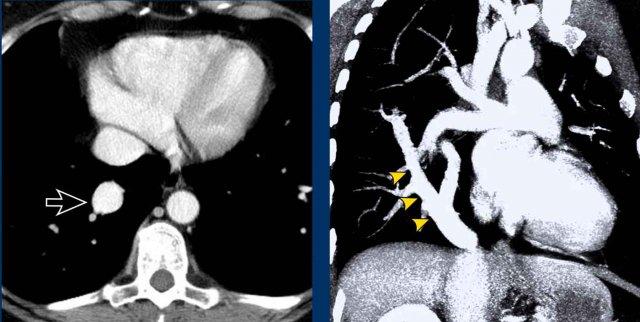

Tĩnh mạch Scimitar là một dạng PAPVR của phổi phải dẫn lưu xuống dưới tim, thường nhất là vào tĩnh mạch chủ dưới.

PAPVR của thùy dưới phải, dẫn lưu máu vào tĩnh mạch chủ dưới. Đây còn được gọi là tĩnh mạch Scimitar, do hình dạng của nó giống với một loại kiếm cong.